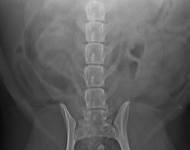

MVDr. Meloun: Lumbosakrální přechodový obratel